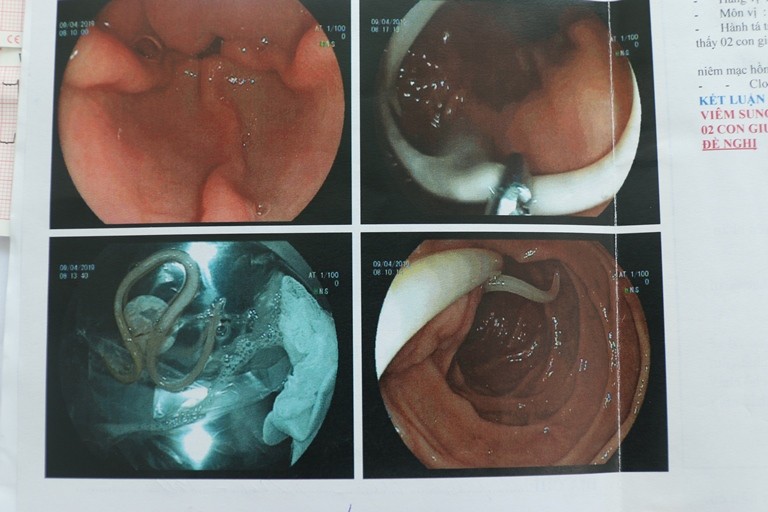

Hai con giun đũa trong tá tràng cua

Hai con giun đũa trong tá tràng cua Khai thác tiền sử cho thấy người bệnh và gia đình có thói quen thích ăn rau sống. Bs Nông Đức Thắng – BS điều trị chính, cho rằng đây là nguyên nhân dẫn đến tình trạng nhiễm giun đũa của chị. Giun đũa là một loại ký sinh trùng sống ở ruột người, là loại giun tròn, có kích thước lớn. Điều kiện quyết định sự lây truyền của giun đũa là tình trạng vệ sinh, các thói quen sinh hoạt và ăn uống, mức độ tiếp xúc với đất bẩn nhiễm phân người. Bệnh không lây truyền trực tiếp từ người qua người mà do người nuốt phải trứng giun qua đường ăn uống.